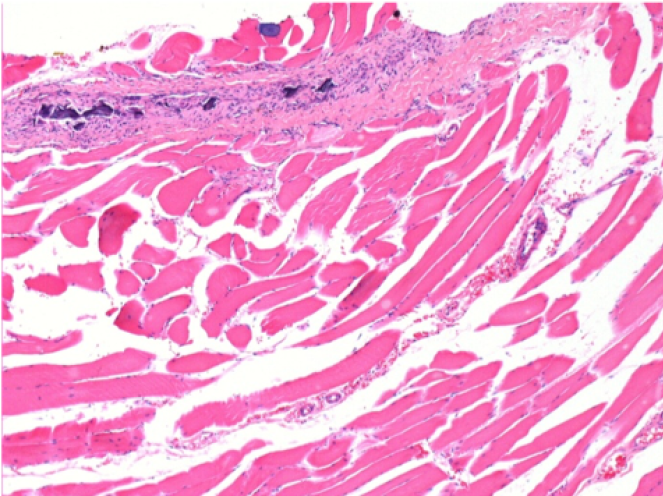

Через 3 місяці (90 днів) після ін'єкції Ендопіл 0,1 мл в правий претибіальний м'яз.

7 місяців (210 днів) після ін'єкції 0,1 мл Ендопіл в правий претибіальний м'яз.

Повна Restitutio ad integrum через 7 місяців